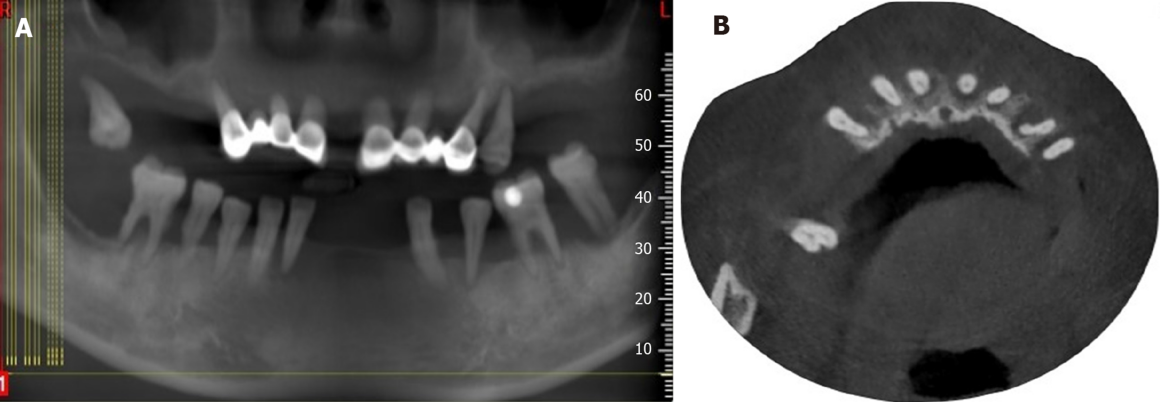

Реабилитация на диоксиде циркония

Проблема: Частичное отсутствие зубов, эстетика , страх стоматологов